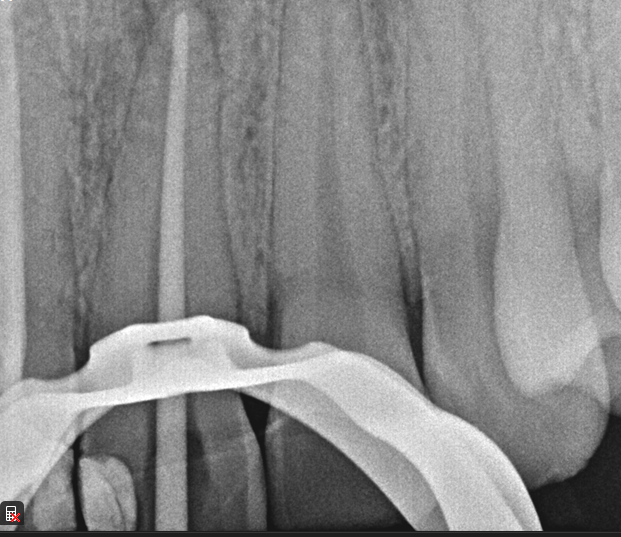

Case: RCT on Tooth #19

45-year-old male, schizophrenia, GERD, eczema, alcohol and methamphetamine abuse, antisocial personality disorder. Allergic to bananas and avocado. On ivermectin, furosemide, and omeprazole.

Dx: Pulp necrosis and symptomatic apical periodontitis without radiographic lesion.

Tx: Root canal therapy initiated.

Reflection

Managing this patient was tough. He was homeless, had psychiatric issues, and very low tolerance—he even walked out mid-treatment. But with patience and a flexible approach, we were able to complete the treatment. A good reminder that sometimes the biggest challenge isn’t the tooth, it’s the person in the chair.